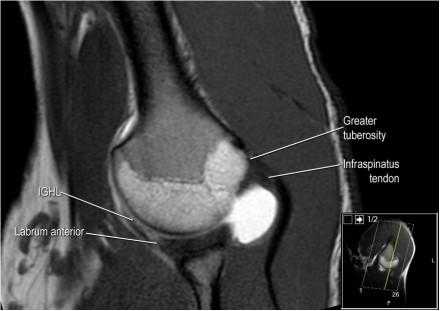

Изображение задних отделов плечевого сустава.

Отображены надостная, подостная и малая круглая мышцы и их сухожилия. Все они прикрепляются к большому бугорку плечевой кости. Сухожилия и мышцы манжеты вращателей участвуют в стабилизации плечевого сустава во время движения. Без манжеты вращателей головка плечевой кости частично сместилась бы из суставной впадины, уменьшив силу отведения дельтовидной мышцы (мышцы вращательной манжеты координирует усилия дельтовидной мышцы). Повреждение манжеты вращателей может привести к смещению головки плечевой кости кверху, в результате вызвая высокое стояние головки плечевой кости.